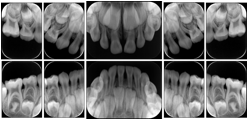

- OO-1. Intra-oral Full Mouth Series Structured Display